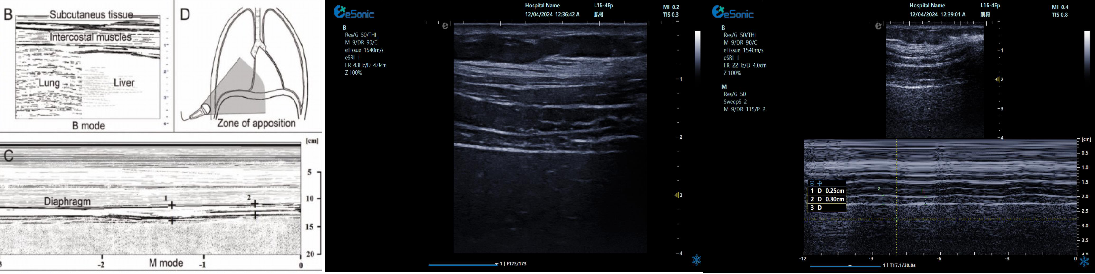

重症肺部超声

超声声像图:声束垂直胸膜线时,可见多条A线与胸膜线平行,且等间距。

膈肌超

评估内容:膈肌移动度、膈肌厚度、增厚率。

评估意义:判断病人膈肌功能,呼吸功能,脱机前后评估等

常用检查模式:B、M

检查探头:凸阵、线阵

对超声设备要求:M型、解剖M型;测量快速准确;有专用的测量包

膈肌厚度检查

探头:高频线阵探头

部位:放置于腋前线与腋中线,7/8肋间或8/9肋间,沿肋间隙放置,观察和测量膈肌的厚度。

功能:M型超声,膈肌测量包

膈肌厚度变化

膈肌厚度测量

呼气末膈肌厚度正常值为2.0-3.5cm

膈肌活动度检查

探头:低频探头

部位:放置在腋前线或锁骨中线与肋缘交界处,启用M模式取样线垂直于膈肌,观察和测量膈肌运动幅度。

功能:M超,膈肌测量包

膈肌活动度测量